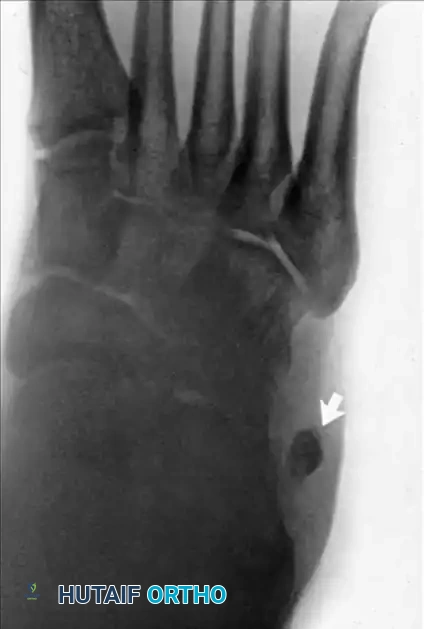

Figure 82-47: (A) A 61-year-old man with a rupture of the peroneus longus tendon and a varus right foot. (B) Note the hypertrophic os peroneum and its proximal migration following the rupture.

- Plain Radiographs: Essential for identifying bone avulsions (e.g., "fleck sign" of the superior peroneal retinaculum) or the proximal migration/fracture of an os peroneum.

Figure 82-48: (A and B) Radiographs demonstrating a tear of the peroneus longus with proximal retraction of the sesamoid bone (os peroneum). (C) T2-weighted MRI showing a type I tear of both the peroneus longus and peroneus brevis tendons.